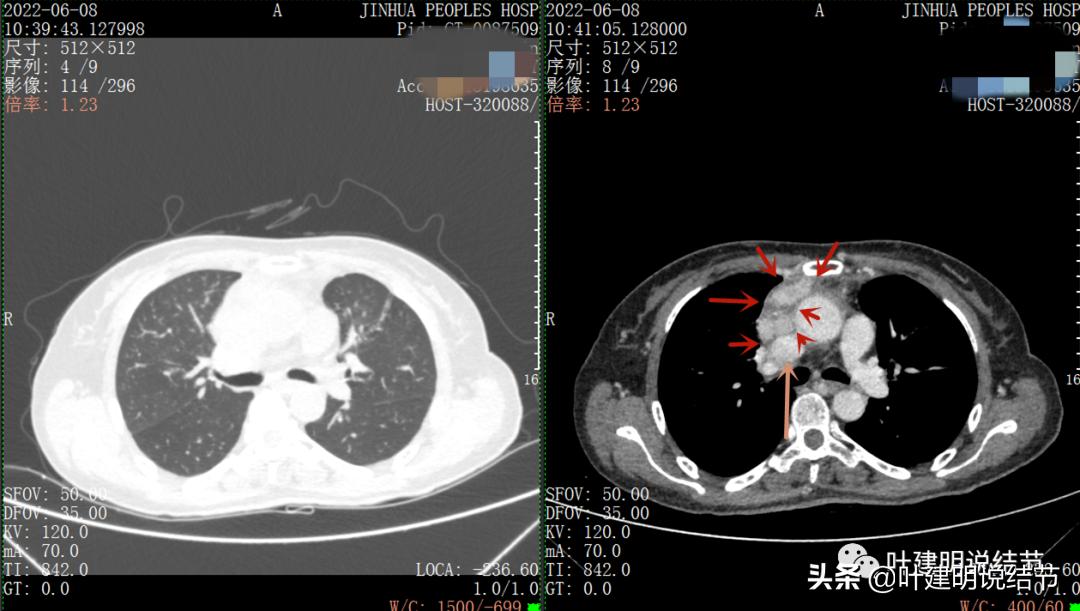

再来看看她的CT增强图像:

以下图片左侧是肺窗,右侧是纵隔窗。红色箭头示病灶,桔色箭头示无名静脉,黄色箭头示支气管,砖色箭头示上腔静脉,蓝色箭头示主动脉,紫色箭头示肺动脉。

病灶胸顶较高位置就出现了,在无名静脉水平

无名静脉略受压